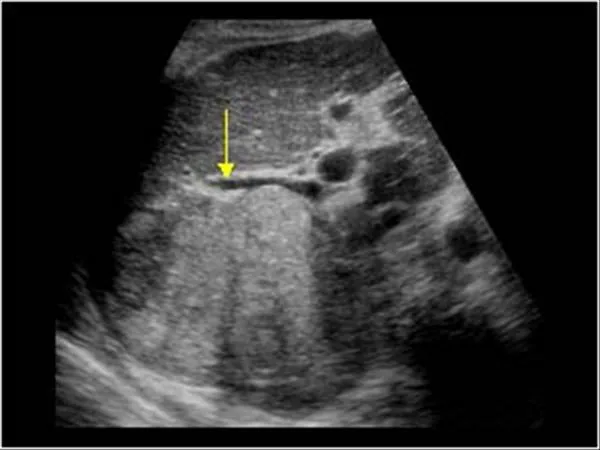

- HCC Surveillance:

- Ultrasound (US) +/- Alpha-fetoprotein (AFP) every 6 months.

⭐ High-Yield Fact: Patients with cirrhosis who develop a new hepatic mass on ultrasound should undergo a triple-phase CT scan or MRI for definitive diagnosis of hepatocellular carcinoma (HCC). Biopsy is often deferred due to bleeding risk.